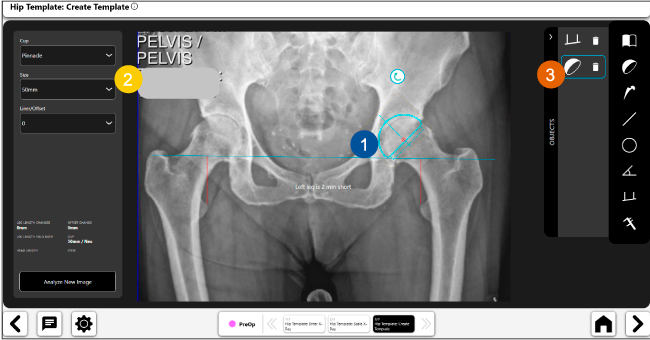

Planeación preoperatoria mediante la creación de plantillas digitales para reemplazo de cadera y análisis intraoperatorio

Disponibilidad de plantillas digitales de cadera.

Expediente histórico y personalizado, optimiza la planeación con el calendario de casos realizados en Velys TM y utiliza los íconos interactivos para una rápida revisión.

Espacio colaborativo: puede compartir los casos entre cirujanos y sus equipos mediante la funcionalidad de intercambio de información.

Anotaciones digitales y herramientas de análisis de longitud de pierna.